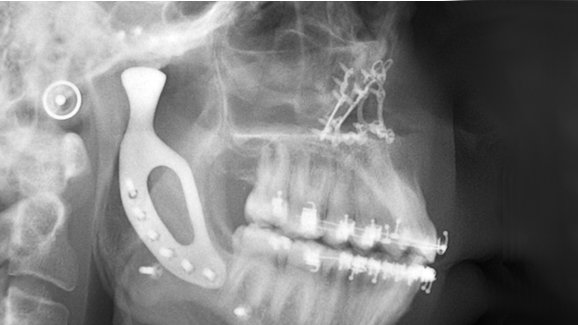

El paciente, Richard Stratton, nació con aplasia del cóndilo, un defecto en el desarrollo del cóndilo mandibular. Le faltaba una articulación temporomandibular, lo que dio lugar a una falta de crecimiento en el lado izquierdo de su rostro y a una mandíbula notablemente sesgada. La condición le afectó también el movimiento de la mandíbula, la capacidad de masticación y la expresión facial.

La mandíbula fue reconstruido quirúrgicamente con una nueva prótesis de titanio. fabricada utilizando la última tecnología de impresión de metal en 3-D, que fue desarrollada y probada en colaboración con 3D Medical, uno de los proveedores de tecnología médica y atención sanitaria líderes de Australia.